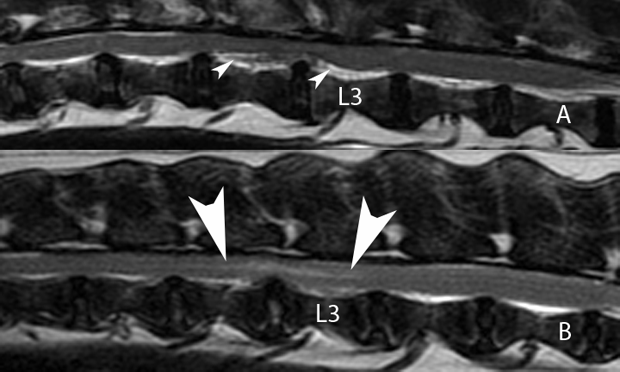

61UWIqrokYL.jpg。Autologous fibroblasts induce fibrosis of the nucleus。Intervertebral Disk Herniation。令和6年産 新米コシヒカリ 5.キロ。

。Frontiers | Intervertebral disc degeneration—Current。[A01151548]動画で見る音声障害 Ver.1 [DVD] (1) 日本音声言語医学会。[A01371176]リウマチ生活指導 (リウマチのリハビリテ-ション (第1集)) 椎野 泰明。[A01206585]泌尿器ケア 13年9月号 18ー9―泌尿器科領域のケア専門誌 泌尿器科術前・術後のケアマニュアル [単行本]。[A01438740]膠原病診療ノート―症例と文献の分析に基づく実戦的マニュアル 三森 明夫。Doctor Stories Dr.コトー診療所のモデル。[A11076679]消化器内視鏡 第24巻11号 20 これは役立つ十二指腸病変アトラス (消化器内視鏡2012年11月号) 消化器内視鏡編集委員会。[A01214448]救急医学 2012年 01月号 [雑誌]。[A11849401]非浸潤性乳管癌のすべて [単行本] 秋山 太。[A12284976]スラッター 小動物の外科手術(全2巻)